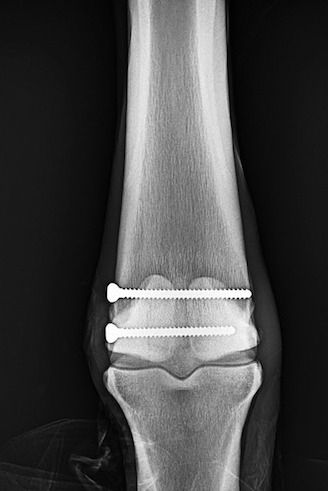

A condylar fracture is a repetitive strain injury that results in a fracture to the cannon bone above the fetlock due to large loads transmitted over the cannon bone during high-speed exercise. On a radiograph, a condylar fracture appears as a crack that goes laterally up the cannon from the fetlock joint and out the side of the bone, essentially breaking off a corner of the cannon bone, sometimes up to six inches long.

Once the injury is identified as a condylar fracture, Palm Beach Equine Clinic surgeons step in to repair the fracture and start the horse on the road to recovery. Depending on the surgeon’s preference, condylar fracture repairs can be performed with the horse under general anesthesia, or while standing under local anesthesia. During both processes, surgical leg screws are used to reconnect the fractured condyle to the cannon bone.

“For a very simple and small non-displaced fracture, we would just put in one to two screws across the fracture,” explains Dr. Davis. “The technical term is to do it in ‘lag fashion,’ such that we tighten the screws down heavily and really compress the fracture line. A lot of times the fracture line is no longer visible in x-rays after it is surgically compressed. When you get that good compression, the fractures heal very quickly and nicely.”

More complicated fractures, or fractures that are fully displaced, may require more screws to align the parts of the bone. For the most severe cases of condylar fractures, a locking compression plate with screws is used to stabilize and repair the bone.